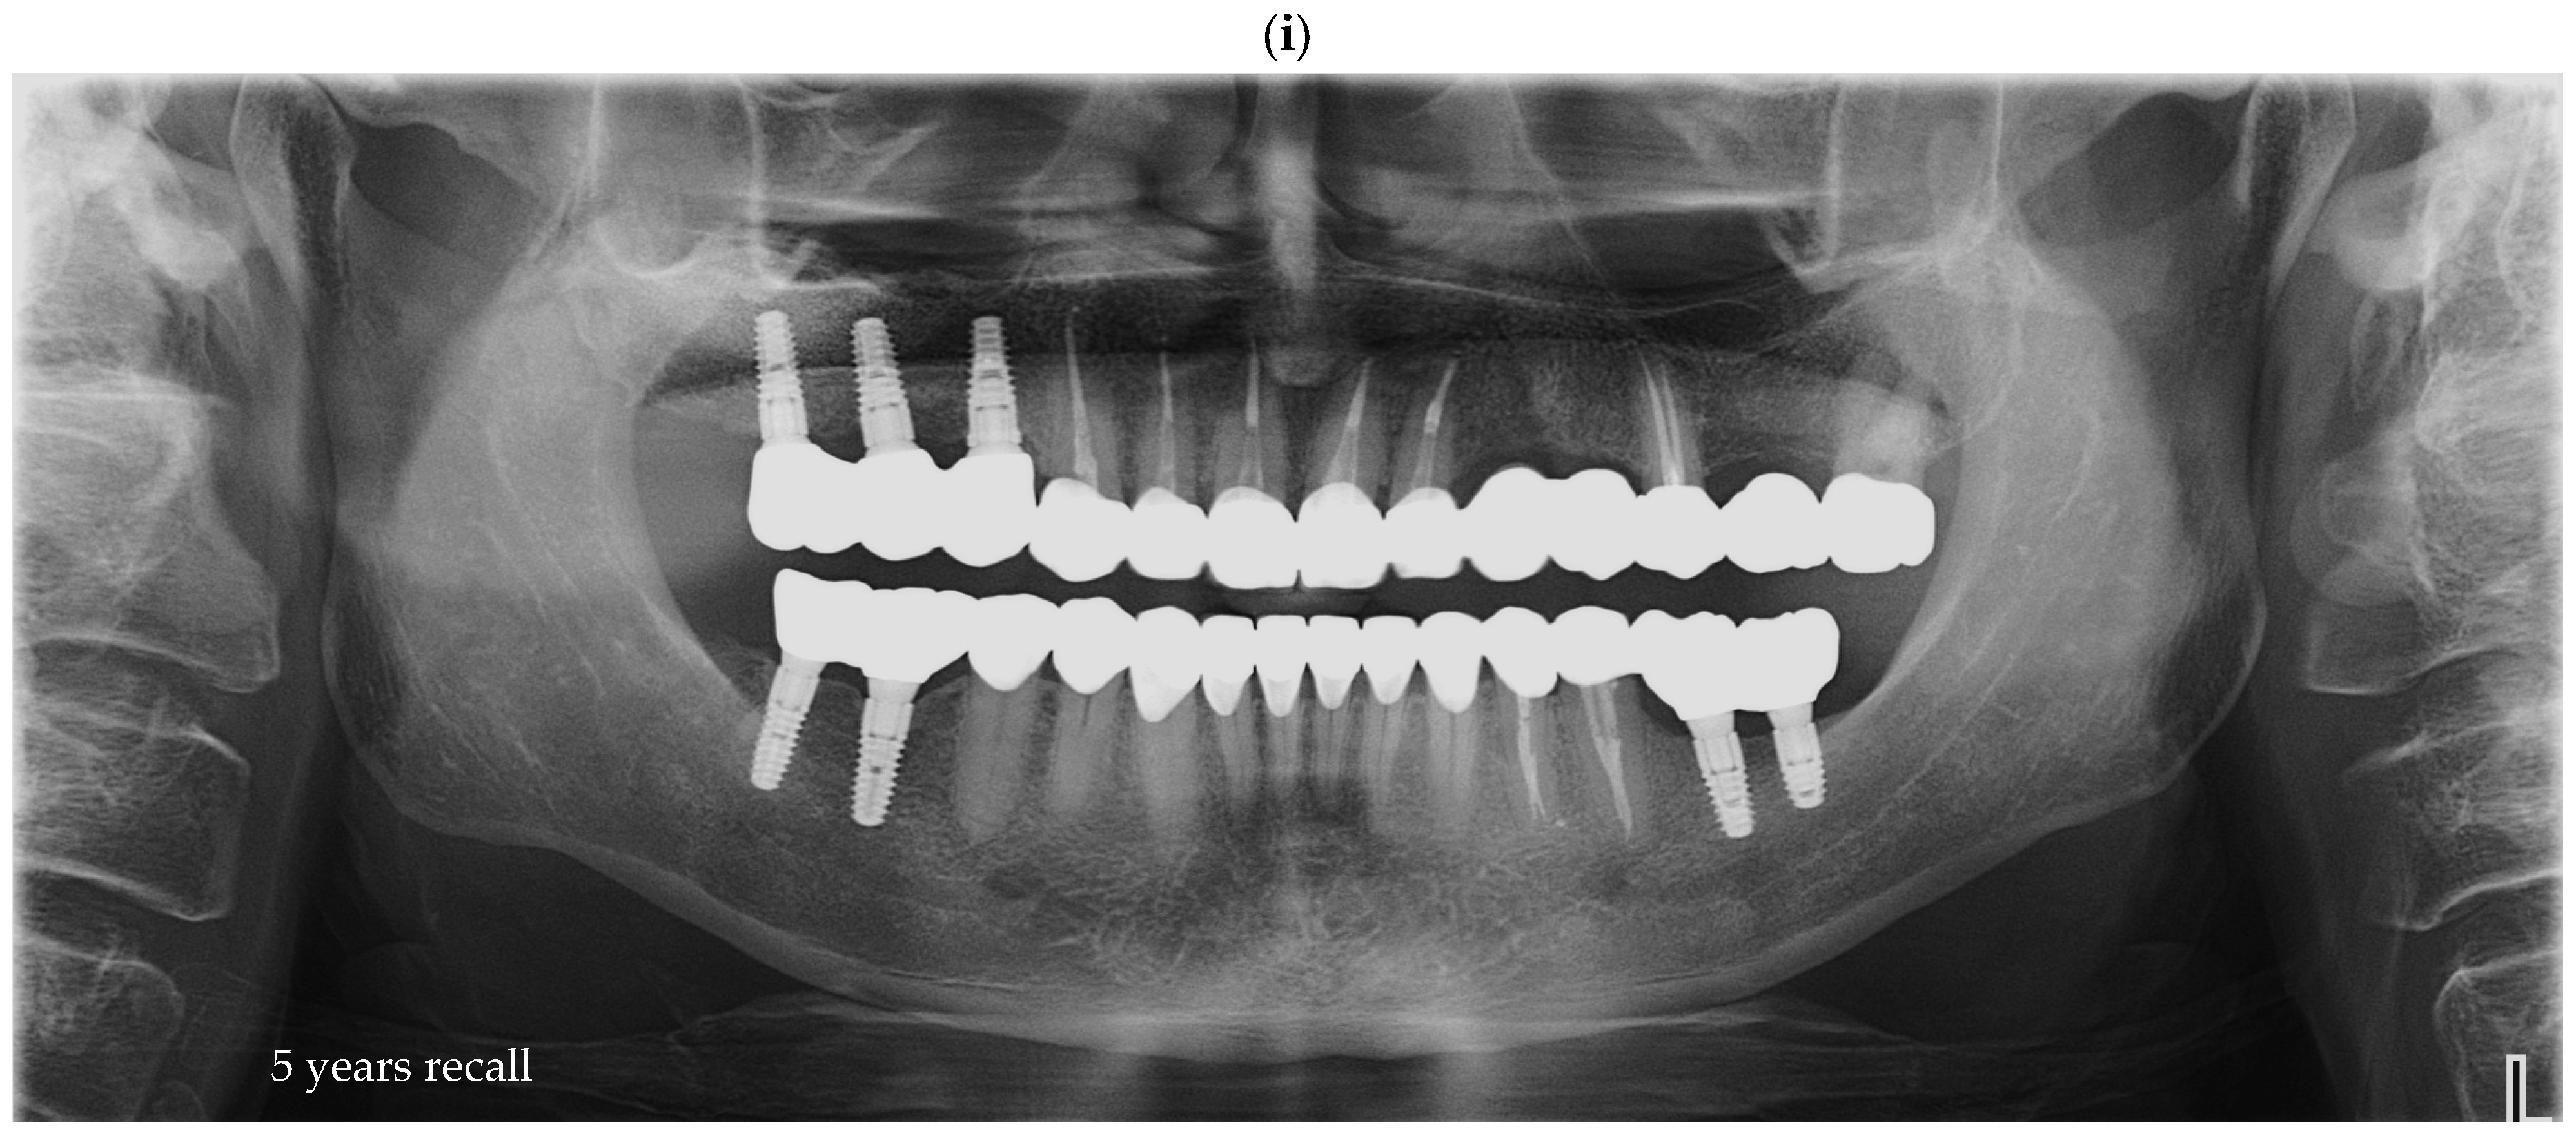

Quantitative comparison of marginal discrepancies was performed using radiographic measurements at the implant–abutment interface (Figure 7b). The presence of vertical gaps, angular misalignments, or overextensions was noted and compared between groups.

Figure 7. OPGs of (a)—case with a perfect fit and (b)—case with misfit of 0.7 and 0.5 mm on implants from position 3.6, respectively, 3.7.